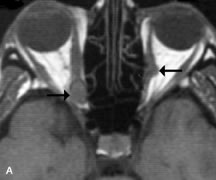

Cystic Lesions

Dermoid cysts appear as rounded, well-defined lesions typically contiguous with an orbital bony suture. The high-intensity signal on T1-weighted images is attributed to the sebaceous-produced lipid contents (Fig. 18).31,50 Mucoceles may demonstrate a hypointense or hyperintense signal on MR images, depending on the concentration of proteinaceous or inflammatory fluid components. The integrity of the bony walls of the expanded sinus cavities cannot be assessed on MR as well as by CT.37,50,55,56 A high-signal intensity on Tl- and T2-weighted images is characteristic of orbital chronic hematic cysts because of the blood-breakdown products within the cysts.57

Fig. 18. A. T1-weighted, (B) T2-weighted fat-suppressed, and (C) T1-weighted fat-suppressed MR scans demonstrate a small dermoid cyst arising near the palpebral portion of the lacrinal gland (arrows). The lesion is similar in signal intensity to fat on the T1-weighted scan (A) consistent with a high adipose tissue content. The lesion shows fat-suppression and low signal intensity on the two fat-suppressed sequences (B and C) confirming its high lipid content.